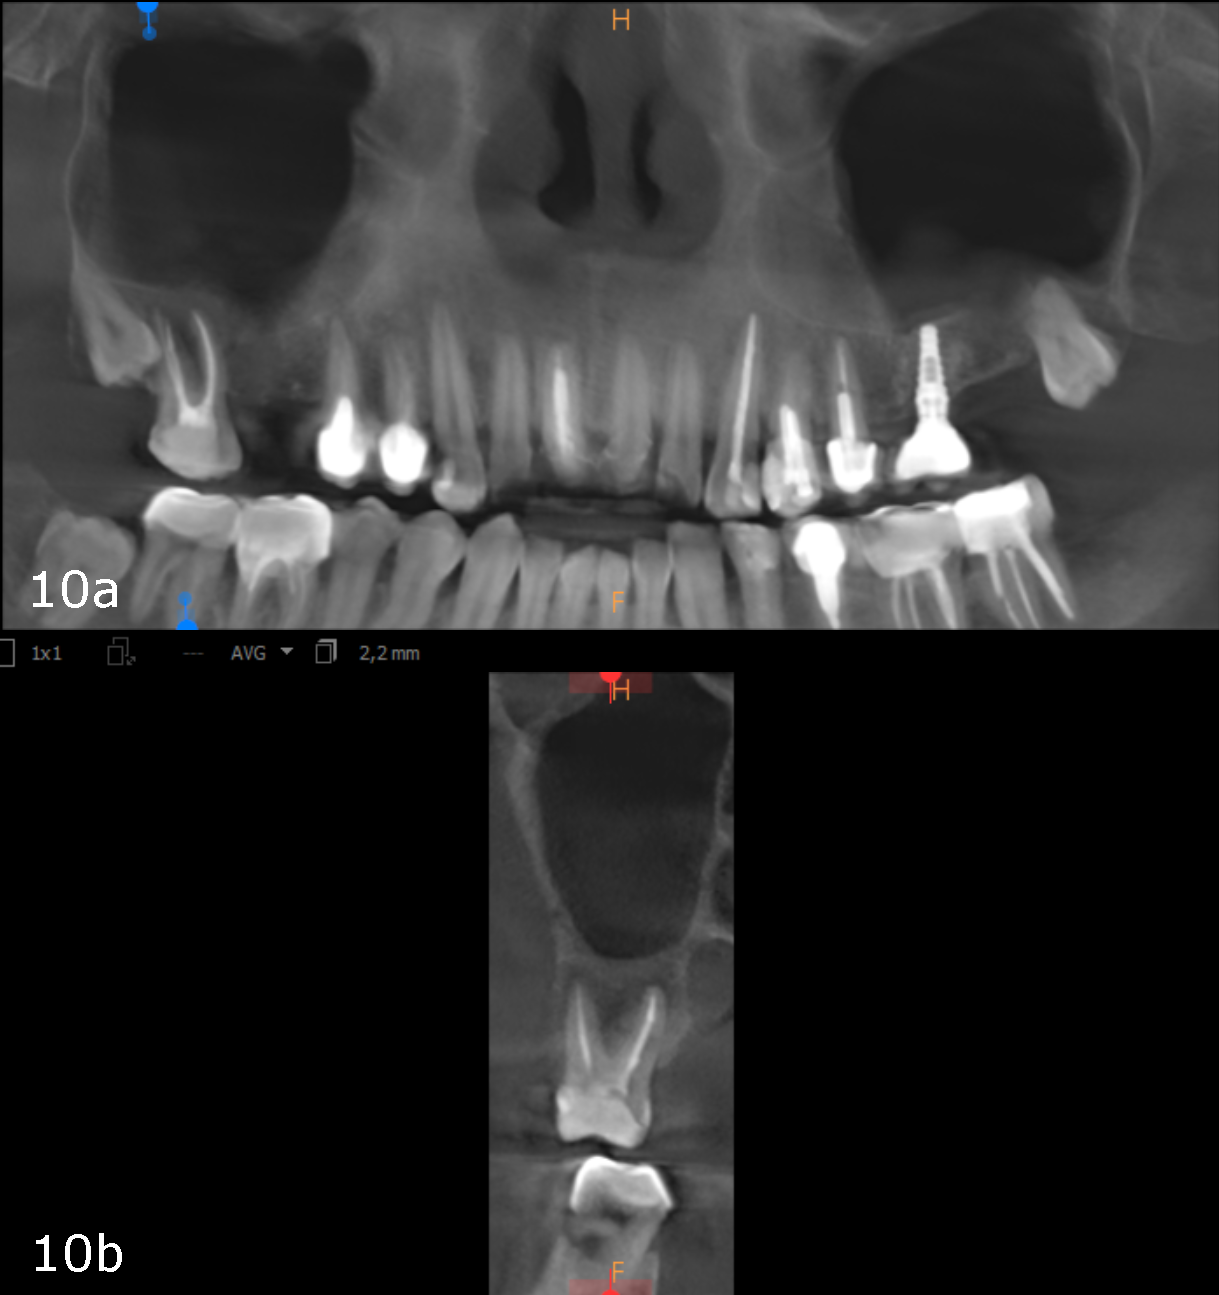

Figs. 10a & b: CBCT scan taken 12 weeks later showing complete healing, panoramic view (a) and cross-section of tooth #17 (b).

The bottom line is that it is really essential to locate the origin of our patients’ problem and evaluate its consequences to give proper treatment that facilitates complete regeneration of not only the periapical area but also the entire area of the paranasal sinuses (Figs. 10a & b). This can help the body and the immune system to achieve miraculous healing with a non-invasive treatment protocol.

As a follow-up, we took a CBCT scan 12 weeks after the obturation, and it clearly showed that both the periapical tissue as well as the paranasal sinuses had recovered fully (Fig. 7). Newly formed cortical and cancellous bone was visible around the buccal and palatal roots (Figs. 8a & b) and extended in the caudal direction. Furthermore, all the paranasal sinuses were clear, and no epithelial widening was visible (Figs. 9a-f).